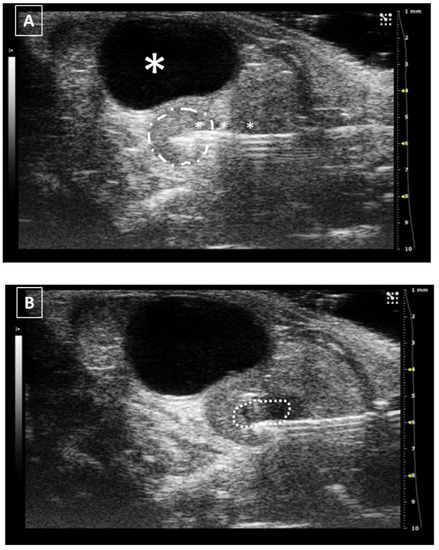

Figure 8. Intrauterine injection. (A) The uterus is punched but no fluid is administered. The needle is marked with white asterisks. The uterus is surrounded by a dashed line. The urinary bladder is marked with a big white asterisk. (B) Same structure after administration. The fluid collection is marked with a dotted line. Images obtained at 40 MHz frequency.

The uterine injection using ultrasonography is one of the most difficult techniques, especially when the organ is in repose (not gravid). The structure is long, thin, and mobile, and the uterine wall is hard. All these characteristics make the intrauterine injection a challenging process. The less mobile part of the uterus is the neck which stays anatomically fixed in place. In this part of the organ, the injection could be feasible. On the other hand, for injecting the uterine horns they should be externally exposed with a surgical opening of the abdomen. For intrauterine injections, the previously published works never went over 30 microliters [37,38,39,40]. Like in the other injections, we should keep the needle in place for some seconds before removing the needle. Figure 8 shows a representative image of a uterine injection.